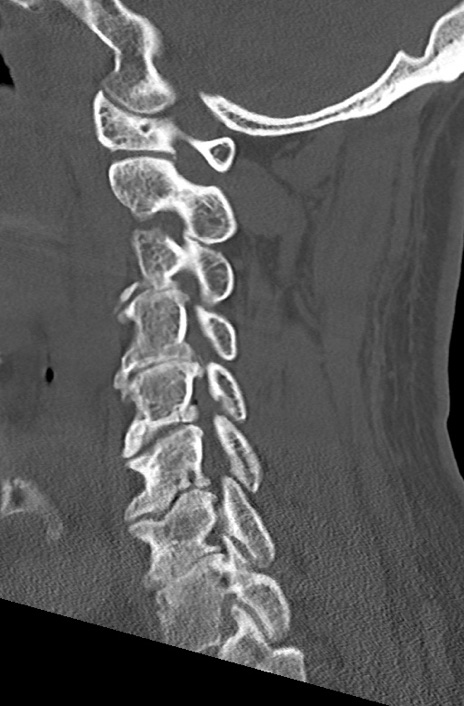

頚椎CT

矢状断像と横断像